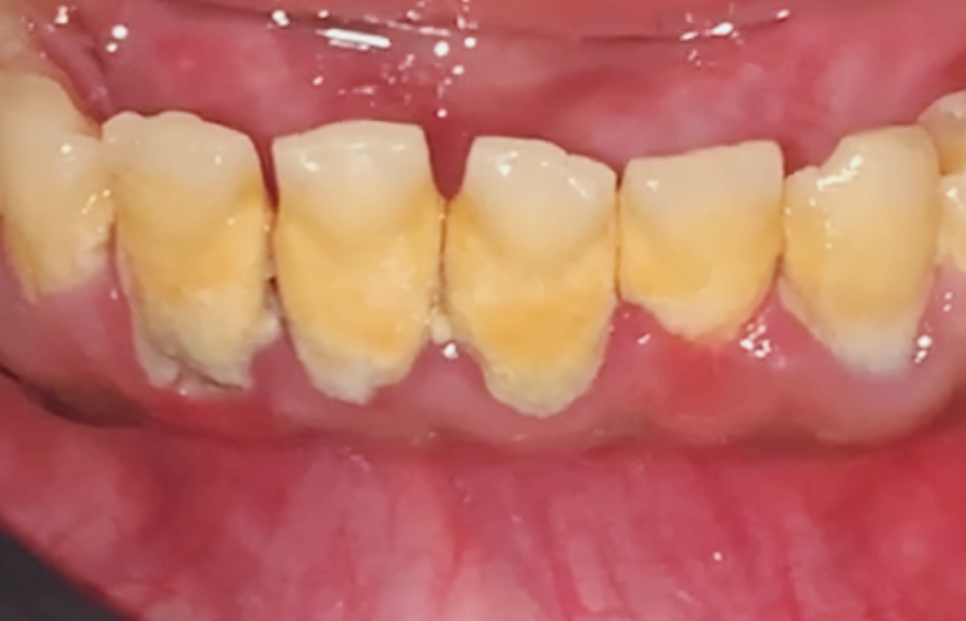

고덕동 스케일링 미루다 앞니 어금니 다 뽑고 임플란트 했습니다.

얼마 전 저희 치과를 찾으신

환자분의 사례를 소개해 드릴게요.

환자분은 오른쪽 아래

예전에 때웠던 보철물이 떨어졌는데,

통증을 참다가 오늘 치아에

금이 쫙 간 것 같다며

극심한 고통과 함께 내원하셨습니다.

진단과 상태

오른쪽 아래는 수직 파절로 인해

치아 금이 쫙 가 있었는데요.